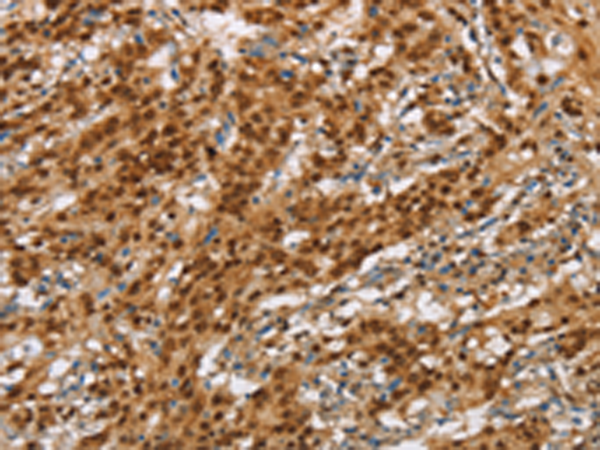

分类: 科研抗体货号: P11572别名: PD1; NACP; PARK1; PARK4应用: IHC反应种属: Human, Mouse, Rat